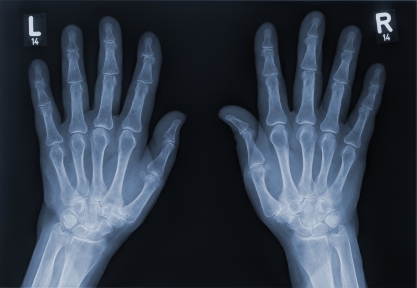

ДИАГНОСТИКА

Основным исследованием при артрите является рентгенография пораженного сустава в двух проекциях. По показаниям проводят артрографию, томографию, электрорентгенографию. При исследовании мелких суставов используют рентгенографию с прямым увеличением изображения. Дополнительную информацию дает термография сустава, ультразвуковое сканирование, радионуклидное исследование.